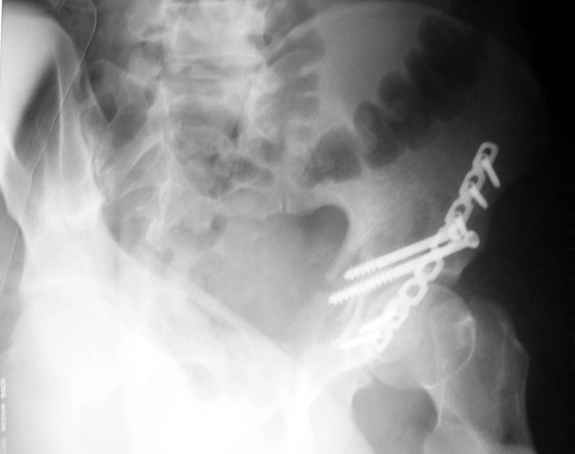

Еще раз спасибо за комментарии и готовность помочь с имплантами. Постоп картинки в приложении,

С наилучшими пожеланиями,

Евгений Чекашкин

К сожалению, набора для ретроградного или антеградного реконструктивного штифтования в операционной нет, поэтому доставка заняла н-ное время. Вопрос, который возник у меня- по поводу оптимальной тактики хирургии: вся фиксация в один этап из расширенного доступа или последовательно сначала бедро и позже реконструкция впадины, комбинированный доступ к впадине отдельно к передней и задней колоннам или из расширенного илеофеморального одного доступа. Все-таки решил остановиться на одноэтапном подходе и спустя 5 дней (как раз и наборы привезли) из расширенного илеофеморального доступа сначала фиксировал реконструктивным штифтом Smith&Nephews бедро и

шейку (благо перелом шейки 2 типа -относительно стабильный) затем фрагмент крыла подвздошной кости Lag screw, далее пластина на заднюю колонну и винты в переднюю колонну.(с размерами и направлением винтов ошибка вышла:-((, но интраоперационно у меня была полная уверенность , что винты *ушли* в лонную кость).